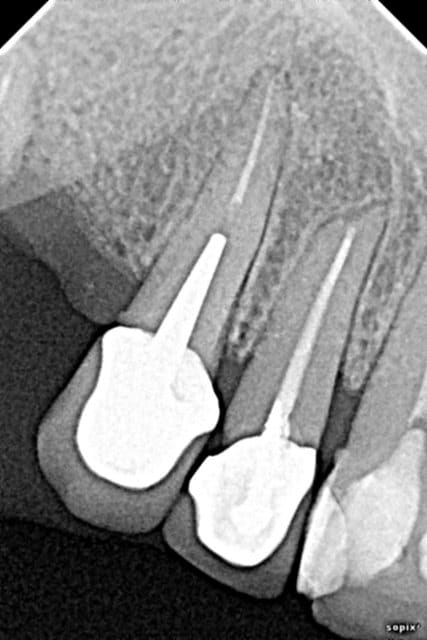

3 sans hésiter (je ne vois pas grand chose sur la pano, trop petite sur mon écran)

Il faut, si on choisi la solution double sinus-lift, faire "vider" le sinus droit avant.

Au scanner, il est complètement obstrué certainement à cause du bout de pâte ou autre que l'on peut apercevoir sur la pano.

La question à 15k€, pourquoi elle a perdu ses dents? Ça commence un peu en bas aussi non, la paro sur molaires ?

Paro pas bonne. Quid des dents du bas et de l'occlusion?